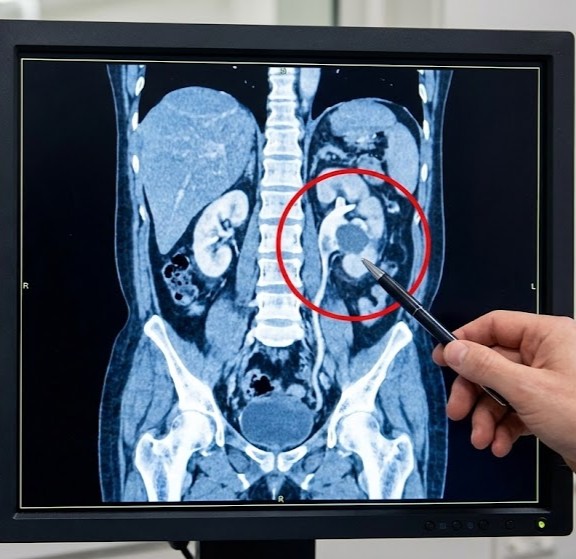

CT-Urografi

Dette er standarden for udredning. Det er en CT-scanning af nyrer og urinveje, hvor man giver kontraststof i en blodåre. Scanningen tages i flere faser, så man kan se præcis, hvordan nyrerne udskiller kontrasten, og om der er “udfyldninger” (svulster) i nyrebækkenet eller urinlederen.